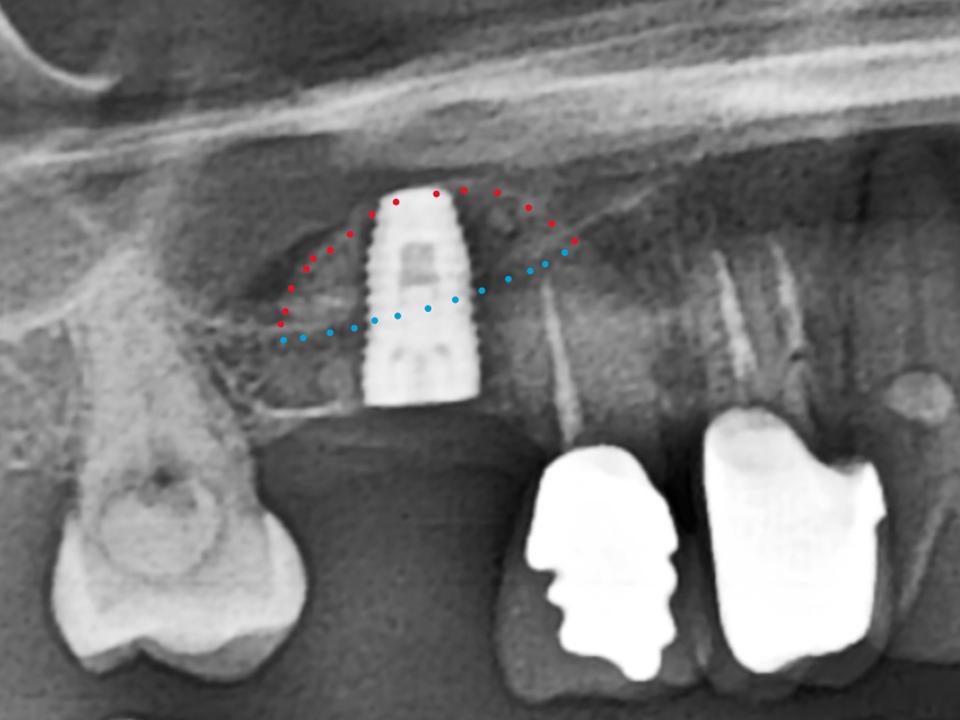

- 高解析AI斷層掃瞄儀:完整顯示骨質狀況及重要神經血管,使植牙都在最安全、最穩固的位置。

- 超音波骨刀:協助完成複雜的手術如自體骨塊移植、狹窄骨嵴、側窗鼻竇提昇…等。

ALL ON全口重建是由4-6 顆植體(依條件而定)成,專為多顆缺牙或全口無牙患者設計的創新全口重建技術,僅需4-6 支植體即可支撐一整排固定式假牙,大幅減少手術次數與成本,並縮短療程時間。